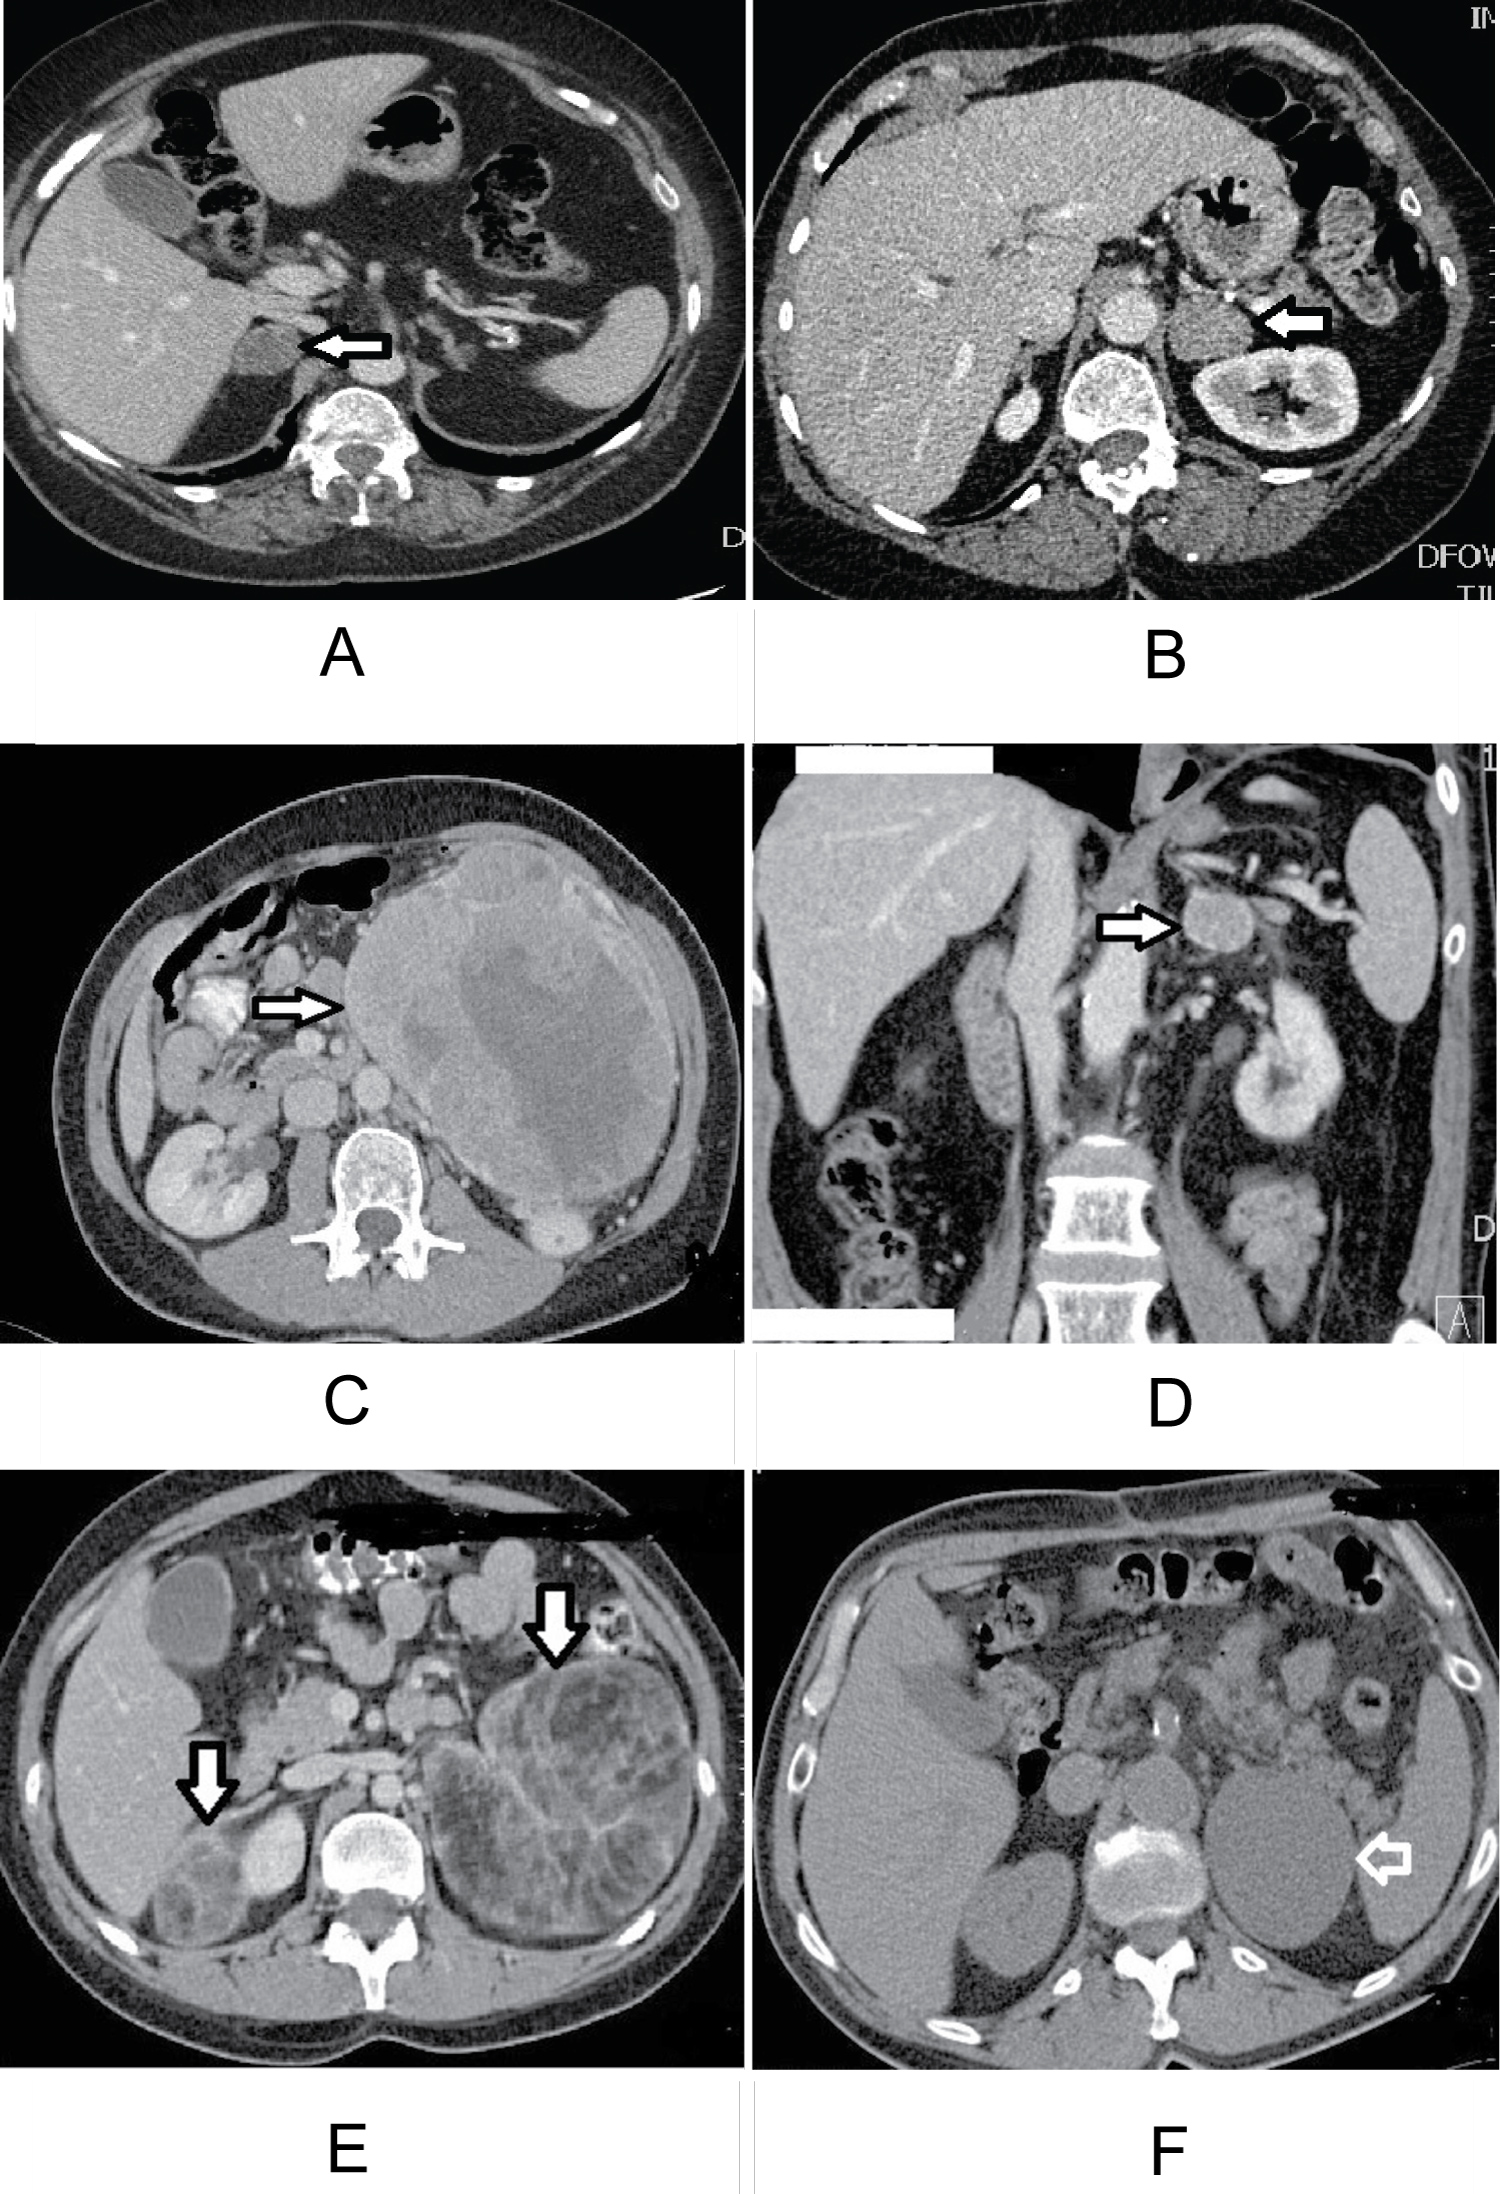

20 patients (22.7%) were diagnosed as non functioning adenoma on clinical/laboratory evaluation; six of them who were hormonally silent and were diagnosed as sub-clinical Cushing, as suggested by the improvement of the general condition postoperatively. 20 patients (22.7%) were diagnosed as functional adrenal adenomas; five of them were diagnosed as Conn's syndrome by pre-operative elevated Aldosterone level +/- hypertension and hypokalemia, 15 patients were diagnosed as cortisol-producing adenoma as proven pre-operatively by high blood pressure and high plasma cortisol levels (Figure 1A and Figure 1B). Three patients were diagnosed as pituitary Cushing and underwent bilateral adrenalectomy. A total of 26 patients was diagnosed as pheochromocytoma as proven by the clinical pictures and increase in the plasma Normetadrenaline and Metadrenaline levels. Five patients were diagnosed as adrenocortical carcinoma and underwent radical adrenalectomy; all the five cancers were left sided (Figure 1C). Four patients were diagnosed as metastatic renal cell carcinoma, three were left sided and one was right sided (Figure 1D).

Figure 1: MSCT abdomen showing (a) Bilateral myolipoma; left 10 × 11 cm, right 4.6 × 3.3 cm; (B) Left adrenal epithelial lined cyst 6.3 × 7.7 cm; (C) Left adrenal metastatic mass, 3 × 2.8 cm; (D) Left adrenocortical adenoma, 30 mm; (E) Left adrenocortical carcinoma 16.8 cm; (F) Right adrenal adenoma 2.8 cm × 2.2 cm. View Figure 1

Two patients were diagnosed as B-cell lymphoma; one underwent right adrenalectomy, and one underwent left radical adrenalectomy. One case was consistent with lung metastasis, and one had a metastatic melanoma. Other cases were diagnosed as cavernous hemangioma, myelolipoma, pseudocyst, true cyst, and two post-operative inflammatory reactions (Figure 1E and Figure 1F), (Table 3).